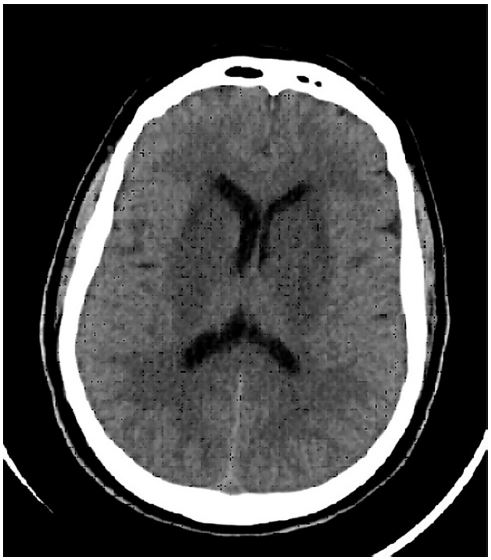

Se presenta el caso de paciente masculino de 47 años con antecedentes de diabetes tipo 2 en tratamiento con hipoglucemiantes orales, de profesión trabajador rural. Ingresa en el Servicio de Emergencias el 26 de diciembre de 2023 por cuadro de delirio asociado a fiebre de 72 horas de evolución (cabe destacar que consultó 48 horas antes por síndrome febril sin foco, el cual fue tratado sintomáticamente con dexametasona y dipirona). Al examen físico se encuentra febril, vigil, desorientado en tiempo, espacio y persona, con trastorno conductual con hiperactividad psicomotriz, discurso desorganizado, temblor esencial en manos y facie, pupilas isocóricas reactivas y simétricas, difícil evaluación de signos meníngeos por el estado el paciente. Ante este cuadro se procede a la realización de pruebas diagnósticas incluyendo laboratorio (pedido de LCR con microbiológico, fisicoquímico y pruebas serológicas para detección del virus de EEO), tomografía de cerebro (que no evidencia lesiones hemorrágicas agudas ni edema cerebral), radiografía de tórax (sin alteraciones parenquimatosas). La punción lumbar informa un líquido cefalorraquídeo incoloro, límpido, con proteinorraquia (1,15 /dL), leucocitosis (60/mm3) con neutrofilia (70%) y lactato aumentado (46,2 mg/dL). La tomografía de ingreso no evidencia signos de sangrado ni desplazamiento de las estructuras medias, con cavidades ventriculares de topografía normal, sin lesiones focales, sin colecciones (Fig. 1). Se solicita electroencefalograma a la espera de los resultados de laboratorio. El electroencefalograma evidenció ritmo alfa occipital, sin asimetrías, tampoco evidencia actividad epileptiforme (Fig. 2). El paciente evoluciona con deterioro del sensorio, requiriendo intubación orotraqueal con posterior traslado a Unidad de Terapia Intensiva. Se inicia tratamiento empírico con aciclovir, ceftriaxona y corticoides sistémicos.

Figura 1. Tomografía realizada el día de ingreso del paciente en Sala de Emergencias.